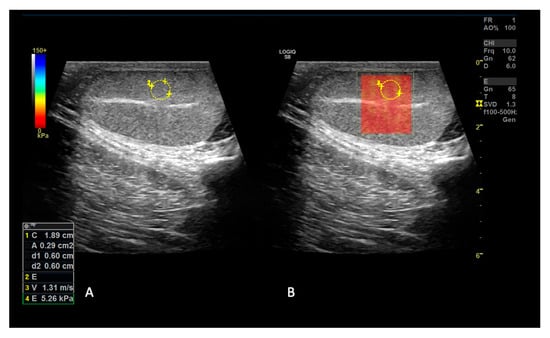

2.1.2. SE and 2D SWE Examination

3.3. 2D Shear Wave Elastography